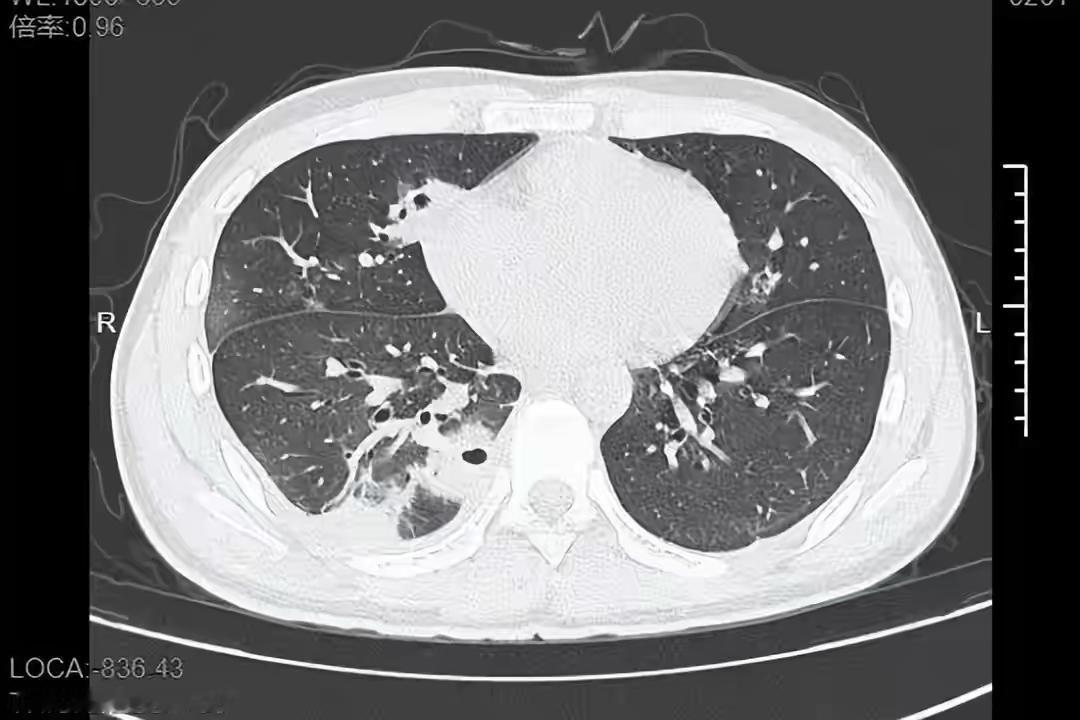

真是惊呆了! 浙江一大学生随手挤了颗痘痘,肺部竟然出了十几个洞?! 医生紧急提醒:这个位置的痘痘,再手痒也别碰! 事情是这样的:20岁的小林(化名)为了备考熬夜,脸上冒了颗黄豆大的痘痘。 他没洗手就对着镜子挤了,结果几天后开始发烧、咳嗽,右胸口像针扎一样疼。 送到医院一查——肺里竟然有十几个空洞,部分肺组织都坏死了!罪魁祸首就是那颗被挤的痘痘! 关键问题出在“危险三角区”! 医生解释,从鼻根到两侧口角的三角区域,血管特别丰富,而且没有“静脉瓣”(相当于血管里的单向阀门)。一旦挤压这里的痘痘,痘痘里的细菌(比如金黄色葡萄球菌)就会顺着血管“直通”全身: 往上可能进颅内,引发脑膜炎、脑脓肿; 往下顺着血液跑到肺部、肝脏,就像小林这样,细菌在肺里“搞破坏”,形成空洞,甚至可能引发败血症、脓毒血症,危及生命! 更吓人的是,这种感染发展的特别快。小林从挤痘到住进ICU,不过短短几天!好在及时治疗,才捡回一条命。 要记住:轻度痘痘别乱干预!皮肤自己会修复,乱涂刺激性产品反而增加风险。 不仅是痘痘,这个区域的任何“小伤口”都要注意清洁。 管住手!别频繁摸脸,手上细菌多,容易污染创口。 出现这些症状马上就医: 疼痛加剧、周围皮肤大面积红肿,伴随发热、乏力、胸痛、咳嗽、呼吸困难! 日常护理小贴士: 用温和的洗面奶洗脸,少吃高糖、高脂、辛辣食物,多喝水,规律作息,减少熬夜——这些都能降低长痘概率! 赶紧转发给身边爱挤痘的朋友,关键时刻能救命! (文章素材来自半岛晨报,侵删)